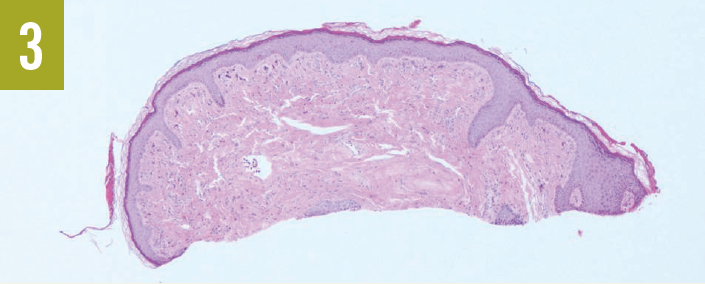

Skin histopathology results showed the epidermis to contain a focus of acantholysis and dyskeratosis. There was a mixed inflammatory infiltrate in the dermis beneath (Figure 3). Periodic acid–Schiff stain results were negative for pathogenic fungi.

Differential diagnoses include seborrheic dermatitis, acrokeratosis verruciformis, benign familiar pemphigus (Hailey-Hailey disease), and transient acantholytic dermatosis (Grover disease). Histopathologic findings of acantholysis and dyskeratosis are the main features of keratosis follicularis. It most often includes a large keratin plug that usually shows focal parakeratosis overlying each lesion. Histopathologic testing can confirm the diagnosis, supported by gene sequencing to observe the mutation in ATP2A2 on chromosome 12.6

Several of the largest facial lesions were removed. Biopsy results confirmed the lesions to be angiofibromas, thereby confirming the TSC diagnosis (Figures 3 and 4).

Figure 3. Biopsy revealed a dome-shaped lesion that was devoid of viral cytopathic effect. (Hematoxylin-eosin–stained sections; magnification x40.)